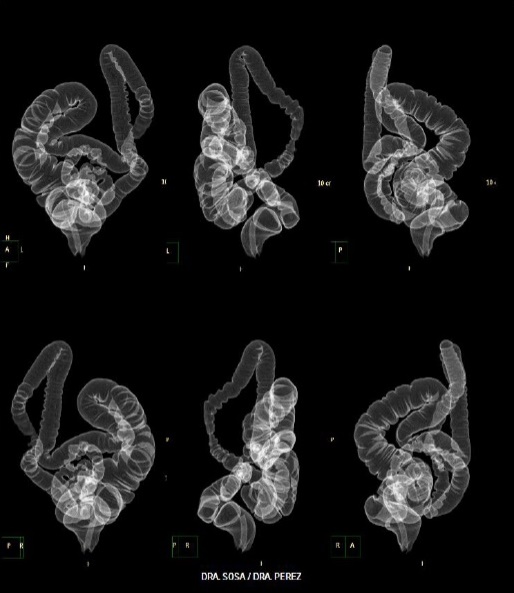

Figura 6 Caso 2: imágenes tomográficas a partir de las cuales se realizó el PPIT; se identifica inicialmente la morfología redundante del colon sigmoides.

Figura 7 Caso 2: imágenes volumétricas del colon desde diferentes perspectivas. Se observa la extrema redundancia del colon en cada una de las partes, desde el colon ascendente hasta el sigmoides.